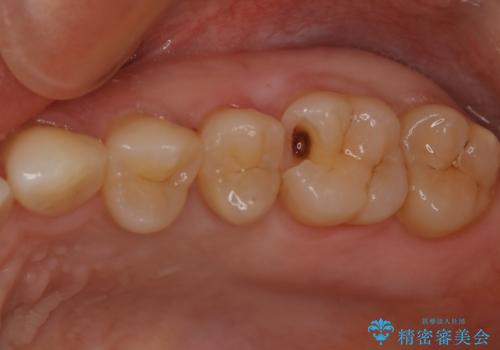

大臼歯 大きな虫歯をセラミックインレーに

- 歯が黒くなってきているのが気になるとのことで、レントゲンを撮影し診断を行いました。

幸い神経までは到達していない虫歯だったため、部分的な詰め物「インレー」で治療を行うこととなりました。